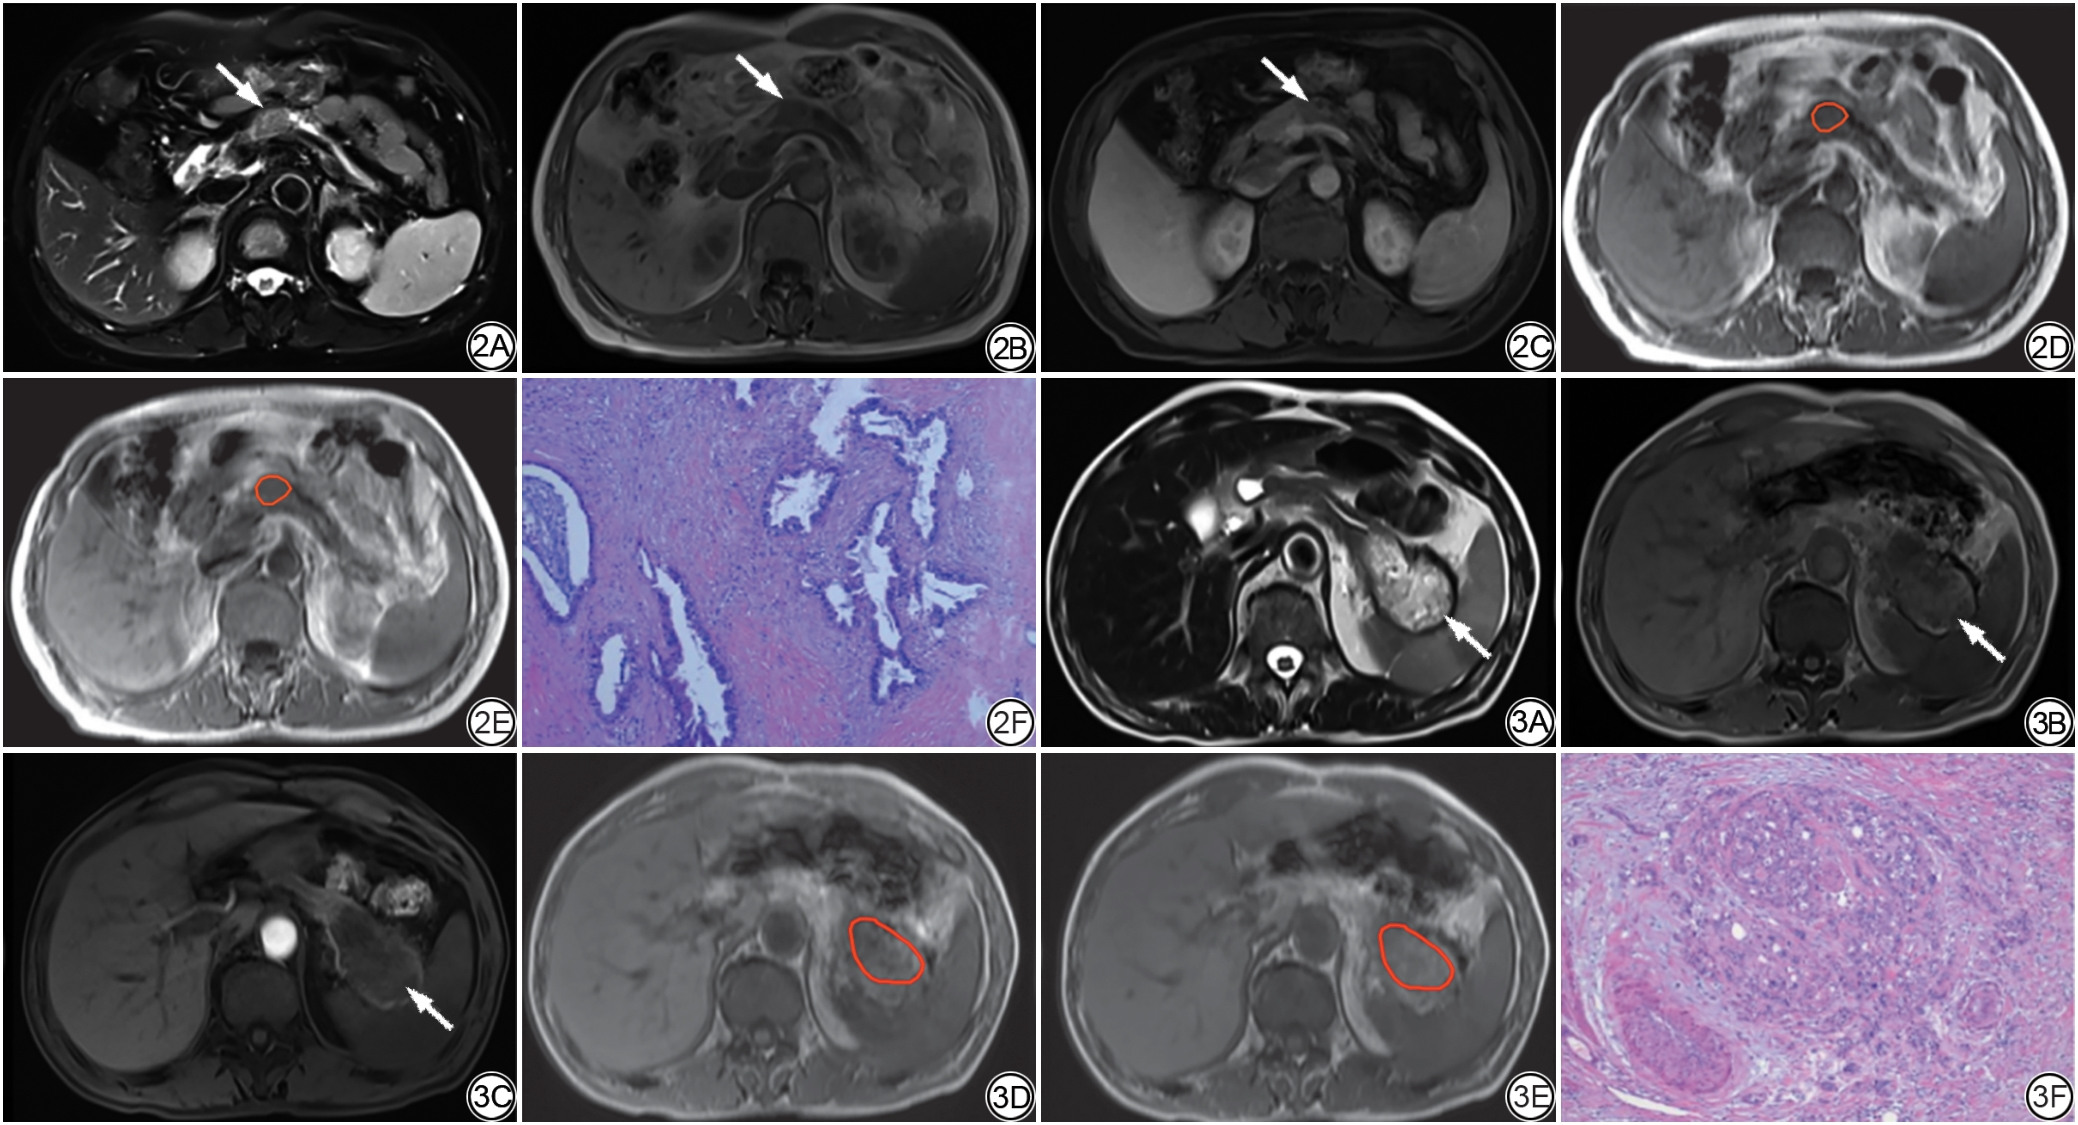

将单因素分析中具有显著差异的参数(年龄与MTR)进一步纳入二元logistic回归分析。为便于解释回归系数,以MTR值×10³后纳入模型,结果显示:年龄、MTR×10³均为PDAC患者病理分级的独立危险因素。详见表2图2, 图3

图2  男,69岁,胰腺体部PDAC。2A:T2WI图像示胰体部见稍高信号结节影(箭),经测量得出最大径为17 mm;2B:T1WI图像示结节影呈稍低信号(箭);2C:T1WI增强门脉期图像示病灶呈不均匀强化(箭),强化程度低于正常胰腺实质;2D~2E:分别为未施加MT脉冲(2D)及施加MT脉冲(2E)的图像感兴趣区勾画,测得的M0=236.73,M1=187.07,则肿瘤的MTR值为0.209;2F:经病理(HE ×100)证实为低级别PDAC。

图3  男,59岁,胰腺尾部PDAC。3A:T2WI图像示胰体部见混杂高信号团片影(箭),经测量得出最大径为64 mm;3B:T1WI图像示团片影呈低信号(箭);3C:T1WI增强动脉期图像示病灶边缘可见强化,内部无明显强化(箭);3D~3E:分别为未施加MT脉冲(3D)及施加MT脉冲(3E)的图像感兴趣区勾画,测得的M0=275.82,M1=202.12,则肿瘤的MTR值为0.267;3F:经病理(HE ×40)证实为高级别PDAC。PDAC:胰腺导管腺癌;MT:磁化传递;MTR:磁化传递率。

Fig. 2  Male, 69 years old, PDAC in the pancreatic body. 2A: T2WI shows a slightly hyperintense nodule (arrow) in the pancreatic body, with a maximum diameter of 17 mm as measured; 2B: T1WI shows the nodule exhibiting slight hypotintensity (arrow); 2C: Contrast-enhanced T1WI portal phase image shows the lesion with heterogeneous enhancement (arrow), with a degree of enhancement lower than that of the normal pancreatic parenchyma; 2D-2E: Region of interest delineation on the images without an MT pulse applied (2D) and with an MT pulse applied (2E) respectively, with a measured M0 = 236.73, M1 = 187.07, respectively, the MTR value of the tumor is calculated as 0.209; 2F: Pathologically (HE ×100) confirmed as low-grade PDAC.

Fig. 3  Male, 59 years old, PDAC in the pancreatic tail. 3A: T2WI shows a heterogeneous hyperintense mass (arrow) in the pancreatic tail, with a maximum diameter of 64 mm as measured; 3B: T1-weighted image shows the mass exhibiting hypotintensity (arrow); 3C: Contrast-enhanced T1WI arterial phase image shows enhancement along the periphery of the lesion without significant internal enhancement (arrow); 3D-3E: Region of interest delineation on the images without an MT pulse applied (3D) and with an MT pulse applied (3E) respectively, with a measured M0 = 275.82, M1 = 202.12, respectively, the MTR value of the tumor is calculated as 0.267; 3F: Pathologically (HE ×40) confirmed as high-grade PDAC. PDAC: pancreatic ductal adenocarcinoma; MT: magnetic transfer; MTR: magnetic transfer rate.